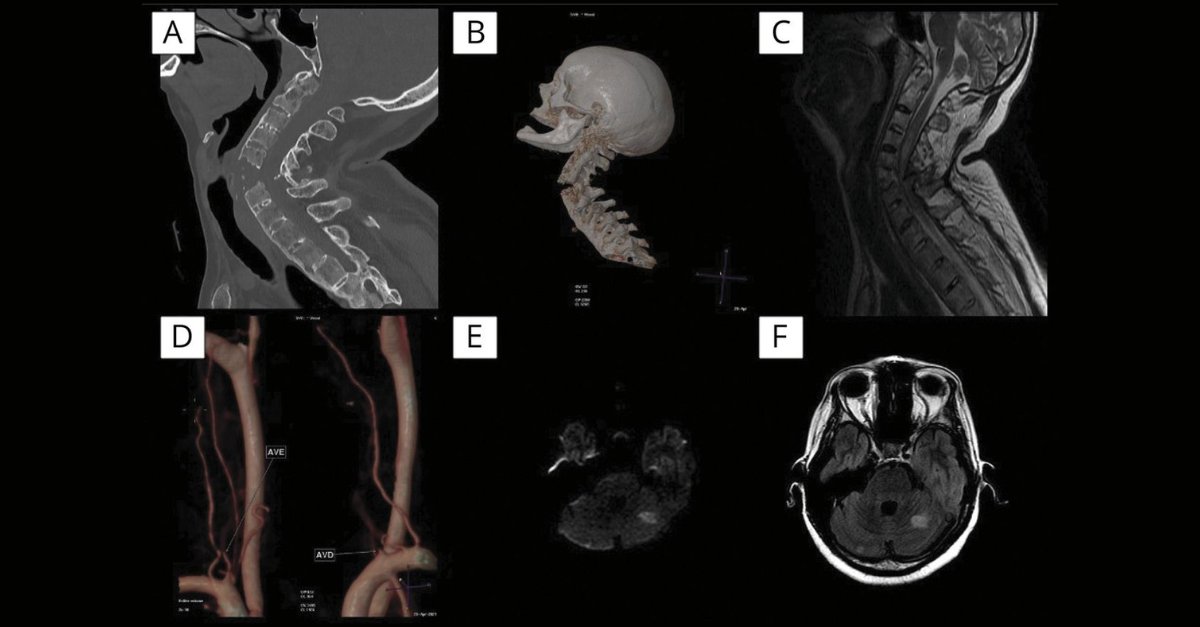

#NeuroImage: Spinal Cord Injury, Vertebral Artery Dissection, and Cerebellar Strokes After Chiropractic Manipulation Learn more: bit.ly/3H16gDI #NeuroTwitter #Neurology

#NeuroImage: Spinal Cord Injury, Vertebral Artery Dissection, and Cerebellar Strokes After Chiropractic Manipulation